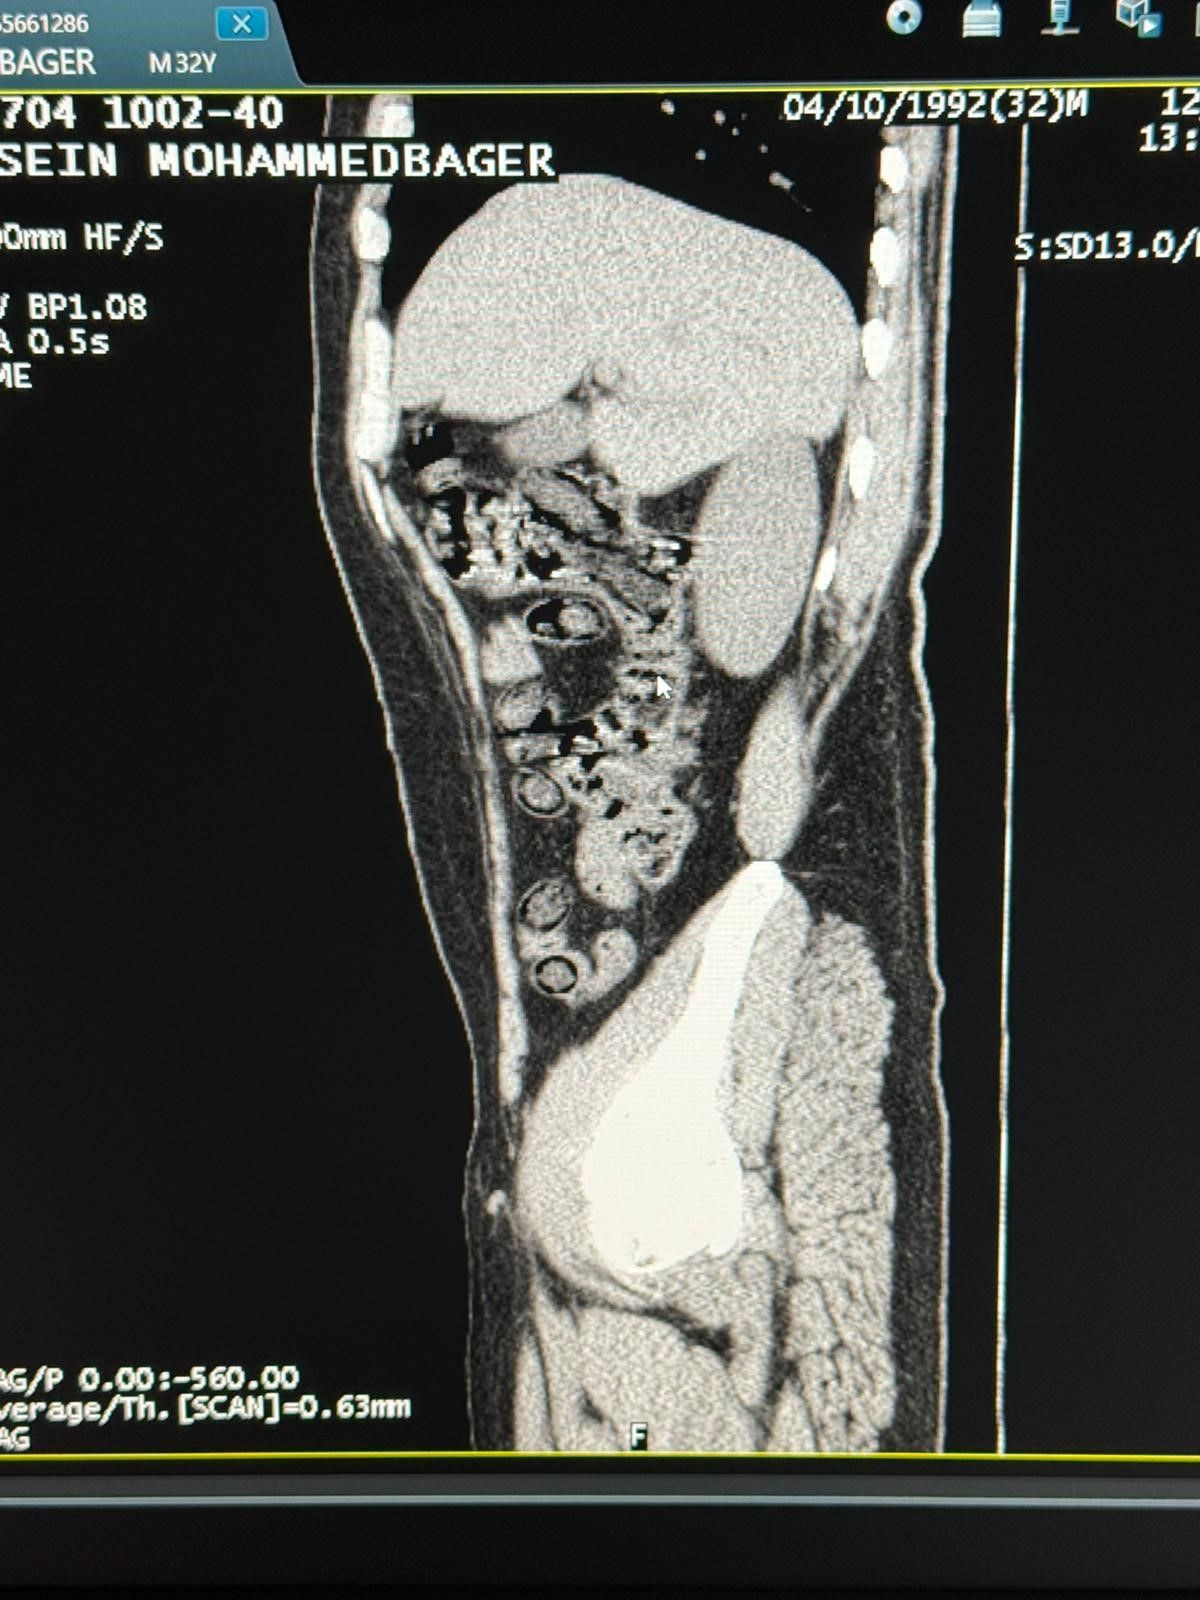

Hastanede yapılan tomografi görüntülerinde, şahısların midelerinde toplam 94 kapsül içinde 928 gram metamfetamin taşıdığı belirlendi. Kapsüller hastane ortamında çıkartılarak muhafaza altına alındı.